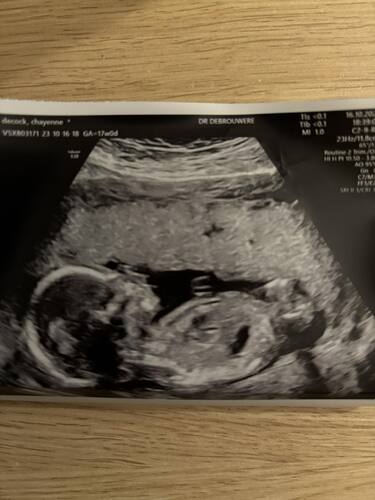

Is nog wel normaal dat je het kindje niet voelt met 17 weken, ik kan niet zien waar de placenta zit in jou geval maar ik voelde de eerste pas met 21 weken en de placenta lag achter (dan voel je het sneller)

Ik hoor inderdaad steeds dat bij de placenta voor je je kindje vaak later voelt, omdat de bewegingen ‘gedempt’ worden door de placenta. Ik kan op echo niet zien waar jouw placenta zit (geen echoscopiste), maar dat zou een verklaring kunnen zijn. Naast het feit dat je nog relatief vroeg in je zwangerschap bent.

Is dat een nieuwe echo, "de 17 weken echo"?

Niet dat ik weet🤷🏻♀️ waarschijnlijk pretecho? Nog altijd de 13 en 20 weken echo aangeboden gekregen deze zwangerschap.

In sommige praktijken maken ze elke keer een echo. Bij mijn praktijk toevallig ook, heb dus een echo gehad met 8 weken, 11 weken, 13 weken echo, 16 weken, 20 weken echo, 24 weken 27 weken, 30 weken, 32 weken, 34 weken, en straks met 36 weer 🤣 maar zijn uiteraard niet allemaal medisch ze kijken dus meestal voor de leuk en luisteren met de echo even naar het hartje (dus niet met een Dopler)